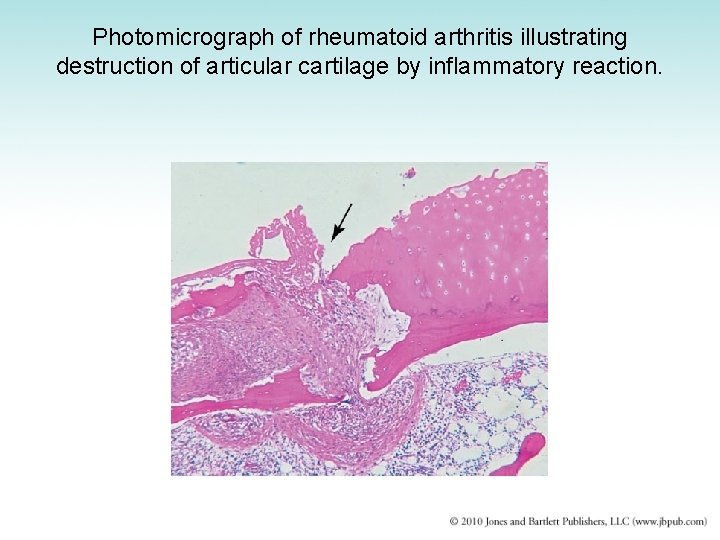

Photomicrograph of rheumatoid arthritis illustrating destruction of articular cartilage by inflammatory reaction.

Photomicrograph of rheumatoid arthritis. Chronic inflammatory reaction in synovium.